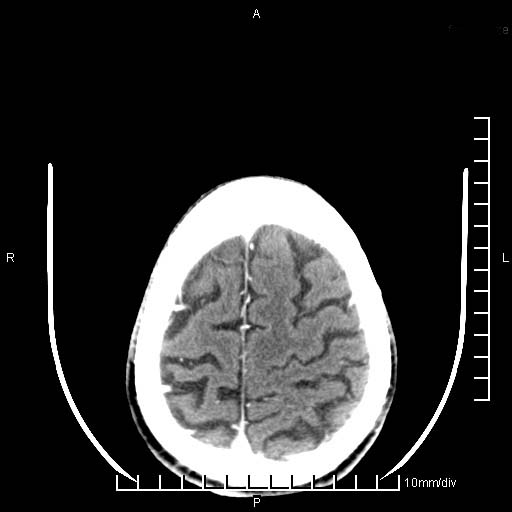

临床以双下肢浮肿,疼痛收治,无明显神经系统症状,既往无梗塞,出血病史。左颞叶见低密度灶,考虑什么?

考虑左侧颞叶脑软化灶。

无强化 无占位 软化灶吧

无强化、 无占位、局部脑沟增宽, 软化灶吧。